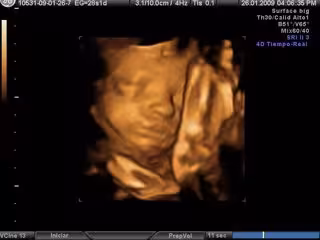

Ecografía en 3D- embarazo